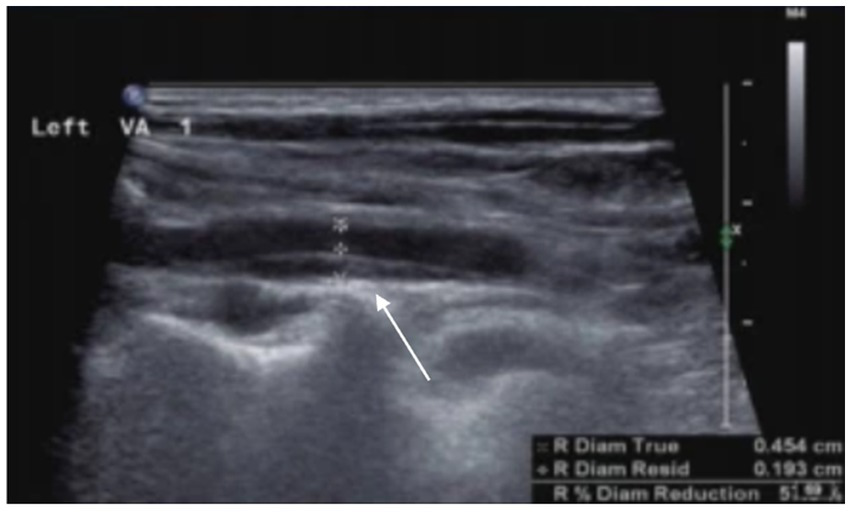

Head and neck vascular US represents a safe, economical, and non-invasive examination method, although its accuracy significantly depends on operator experience and correlates with lesion severity and dissection location. Carotid ultrasonography can observe the lumen and wall structures, which can reveal signs such as the "dual lumen sign," "intramural hematoma," and "intimal flap"(Figure 4).US frequently serves in follow-up evaluations to identify vascular recanalization and remodeling. During the early stages of CAD (particularly within the first 4 weeks), US proves crucial for assessing clinical status and monitoring vascular recanalization (40). Doppler US effectively evaluates in-stent restenosis post-carotid stenting, with pre-discharge US examinations confirming stent patency (41). Research suggests that US monitoring significantly aids in identifying retrograde thrombosis formation and recanalization status in internal carotid artery dissections (42). Reported diagnostic sensitivities for vertebral artery dissection reach 92%, while for cervical artery dissections causing only localized symptoms, sensitivity decreases to 69% (43), indicating potential missed diagnoses of mild stenotic dissections. However, for severe stenotic dissections inducing hemodynamic changes, US achieves sensitivities as high as 96%. Therefore, for clinically concerning cases with negative US results but persistent clinical suspicion, further MRA or CTA examinations are recommended.

Figure 4

Arterial dissection is observed in the left vertebral artery. The posterior wall of the left vertebral artery shows an intramural hematoma, resulting in luminal narrowing, with a residual diameter of 1.9 mm and an original diameter of 4.5 mm.